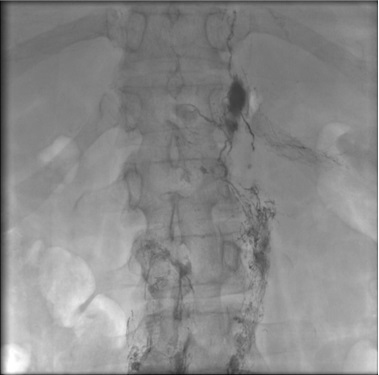

乳糜胸水-腹膜后来源 Chylothorax - Retroperitoneal Flow

腹膜后灌注 Retroperitoneal Perfusion

乳糜胸水 腹膜后来源 Chylothorax - Retroperitoneal Flow